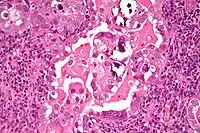

Histology H&E of uterine serous papillary carcinoma. H&E stain. |

Histopathologically, uterine serous carcinomas is typically characterized by (1) nipple-shaped structures (papillae) with fibrovascular cores (2) marked nuclear atypia (irregularities in the nuclear membrane, enlarged nuclear size), (3) psammoma bodies and (4) cilia.